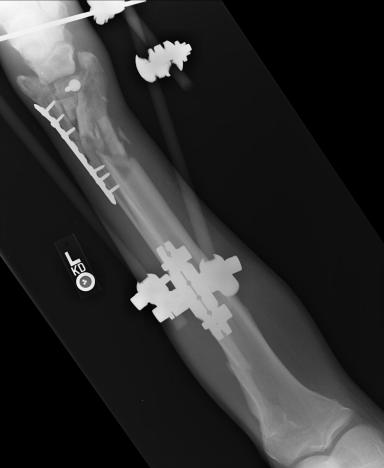

Post-corrective surgery X-Rays of the damaged right & left legs / ankles

The first two x-rays show Liam’s left ankle and pelvis prior to the accident. For comparison purposes it is interesting to see the

differences. The next x-rays were taken after the corrective surgery performed by Dr. Armendariz. Noticed that Dr. Armendariz has used tibia

bracing and also aligned the bone fragments of the left leg so that they could heal in the proper orientation. The external fixation has been

removed and Liam’s left foot has been returned to a more natural alignment.